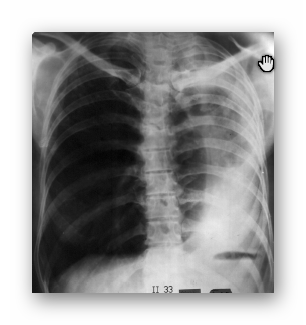

NIEDODMA

RTG

(OBRAZ PRZED I PO USUNIĘCIU CZOPA ŚLUZOWEGO)